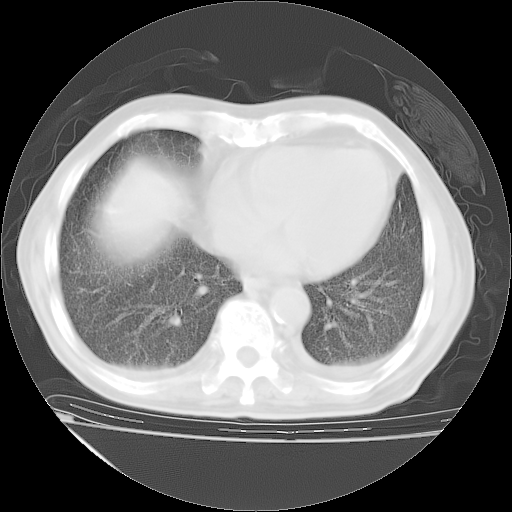

甲强龙80mg/日+抗结核治疗(异烟肼+利福霉素+乙胺丁醇)10天。复查肺部CT。

治疗10天肺部CT

仔细阅读病史资料和CT,我觉得两肺粟粒结核要高度怀疑。

今天带四次肺CT片到市医院,影像科4~5个主任都认为不考虑粟粒性肺结核。主要理由是在3月19日、4月2日、4月27日的CT片没有见到确切异常(肺结核)影像。影像科主任们建议找呼吸内科主任,呼吸内科主任认为首先考虑粟粒性肺结核。